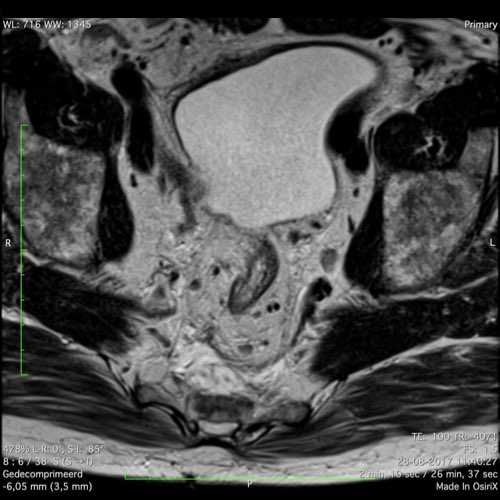

Hình ảnh

Các hình ảnh được cung cấp cho thấy ung thư biểu mô tế bào nhẫn với tình trạng dày lan tỏa thành trực tràng, hình ảnh bia bắn điển hình, và sự xâm lấn mỡ mạc treo trực tràng.